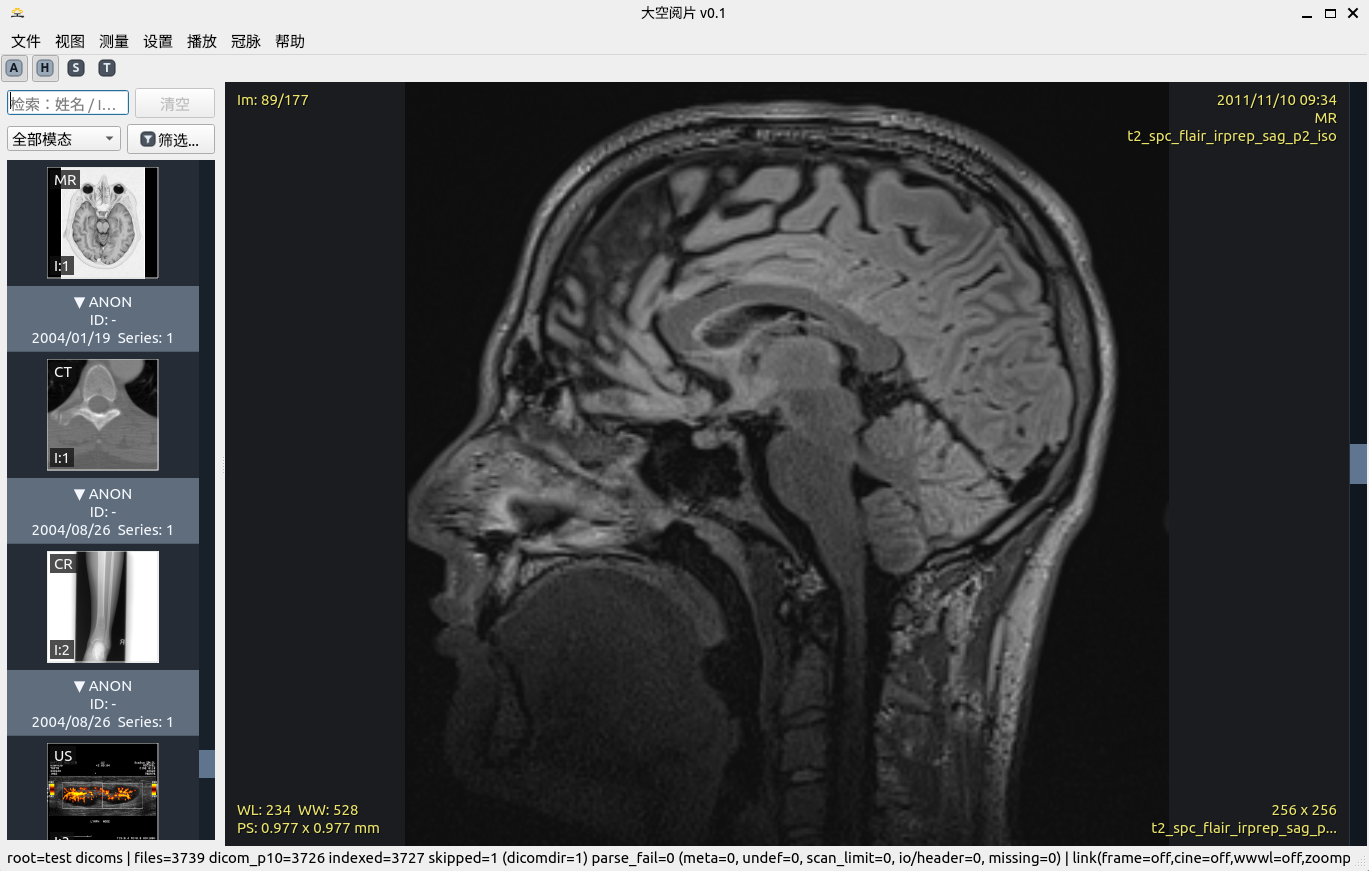

主界面总览

主界面总览:序列树 + 主视口 + 核心菜单入口

临床一线专业阅片工具